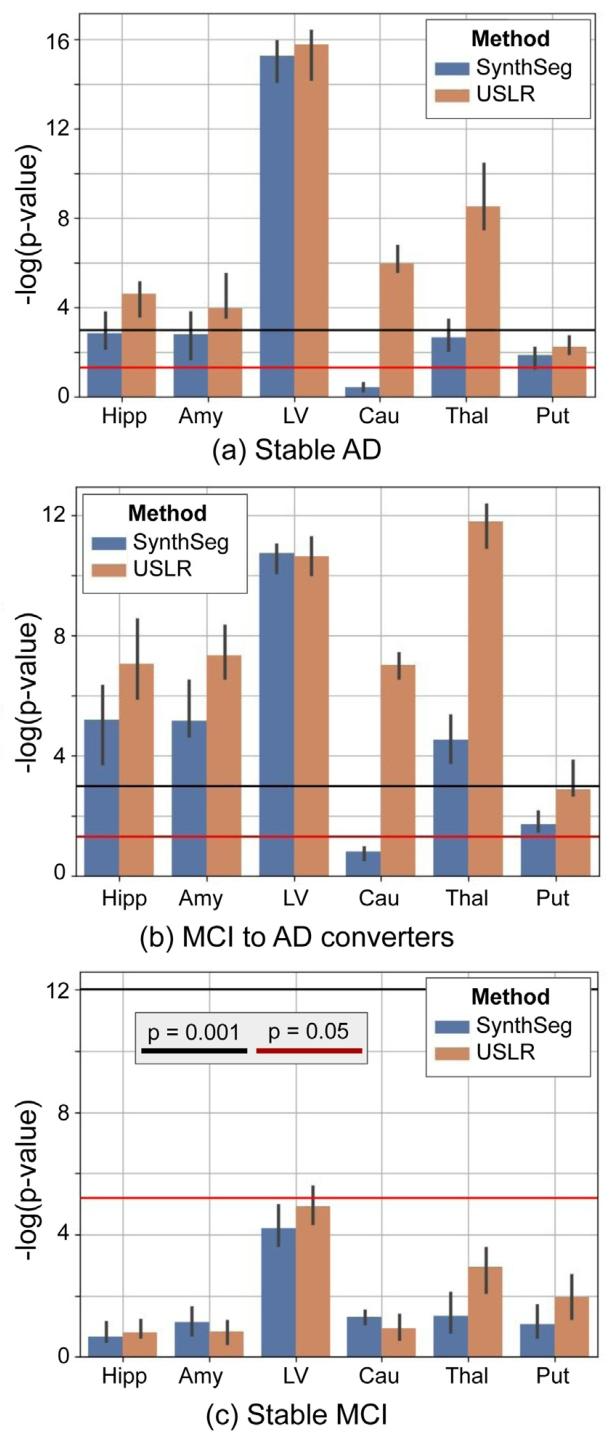

Fig. 12. Linear mixed-effects model with random intercept and slope. The fixed effectsfeatures are time, age, sex, total intracranial volume and the interaction of the interceptand time with diagnosis (stable MCI, MCI to AD converter and stable AD). We plotthe 𝑙𝑜𝑔(𝑝 − 𝑣𝑎𝑙𝑢𝑒) of a contrast comparing time evolution between cognitively normalsubjects and the three diagnostic labels. The bars represent the median value of𝑁* = 1000 bootstrap sample. We compare the USLR framework to SynthSeg. Red linerepresents a 𝑝-value of 5⋅10−2 and the black line a 𝑝-value of 1⋅10−3 . Selected ROIs are:hippocampus (Hipp), amygdala (Amy), lateral ventricle (LV), caudate (Cau), thalamus(Thal) and putamen (Put)

图12 带有随机截距和斜率的线性混合效应模型。固定效应变量包括时间、年龄、性别、总颅内体积,以及截距和时间与诊断结果(稳定型轻度认知障碍(MCI)、从MCI转化为AD的患者、稳定型AD)的交互项。图中绘制了对比认知正常受试者与三种诊断标签受试者时间演变差异的𝑙𝑜𝑔(𝑝值)。误差条代表𝑁=1000次bootstrap抽样的中位数。我们将USLR框架与SynthSeg进行比较。红色线代表𝑝值为5×10⁻²,黑色线代表𝑝值为1×10⁻³。所选感兴趣区(ROIs)包括:海马(Hipp)、杏仁核(Amy)、侧脑室(LV)、尾状核(Cau)、丘脑(Thal)和壳核(Put)。